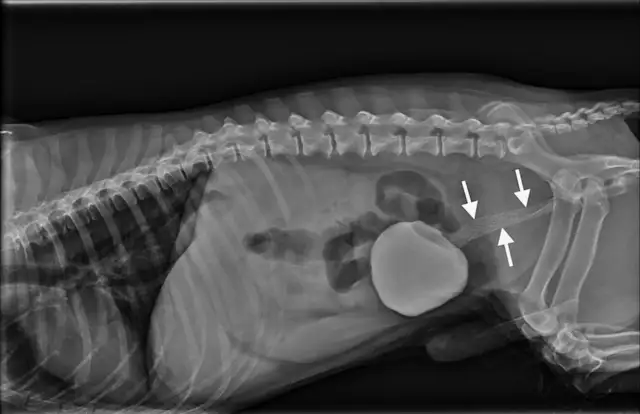

Figure 12A Dog after urethral stent placed to alleviate a complete urinary obstruction secondary to prostatic carcinoma

This 2-view contrast urethrogram shows a 12-year-old neutered male miniature schnauzer just after urethral stent placement for alleviation of a complete urinary obstruction secondary to prostatic carcinoma. The urinary bladder is cranially displaced and moderately distended with radiopaque contrast media. Visible in the left lateral view (Figure 12B), a large, round soft tissue mass caudal to the contrast-filled bladder is consistent with a prostatic mass. A metallic stent (Figure 12B; arrows) spans the entire length of the prostatic urethra and extends a short distance into the trigone of the urinary bladder. The enlarged prostate has caused left lateral displacement of the descending colon. The patient appeared to urinate comfortably immediately after stent placement.